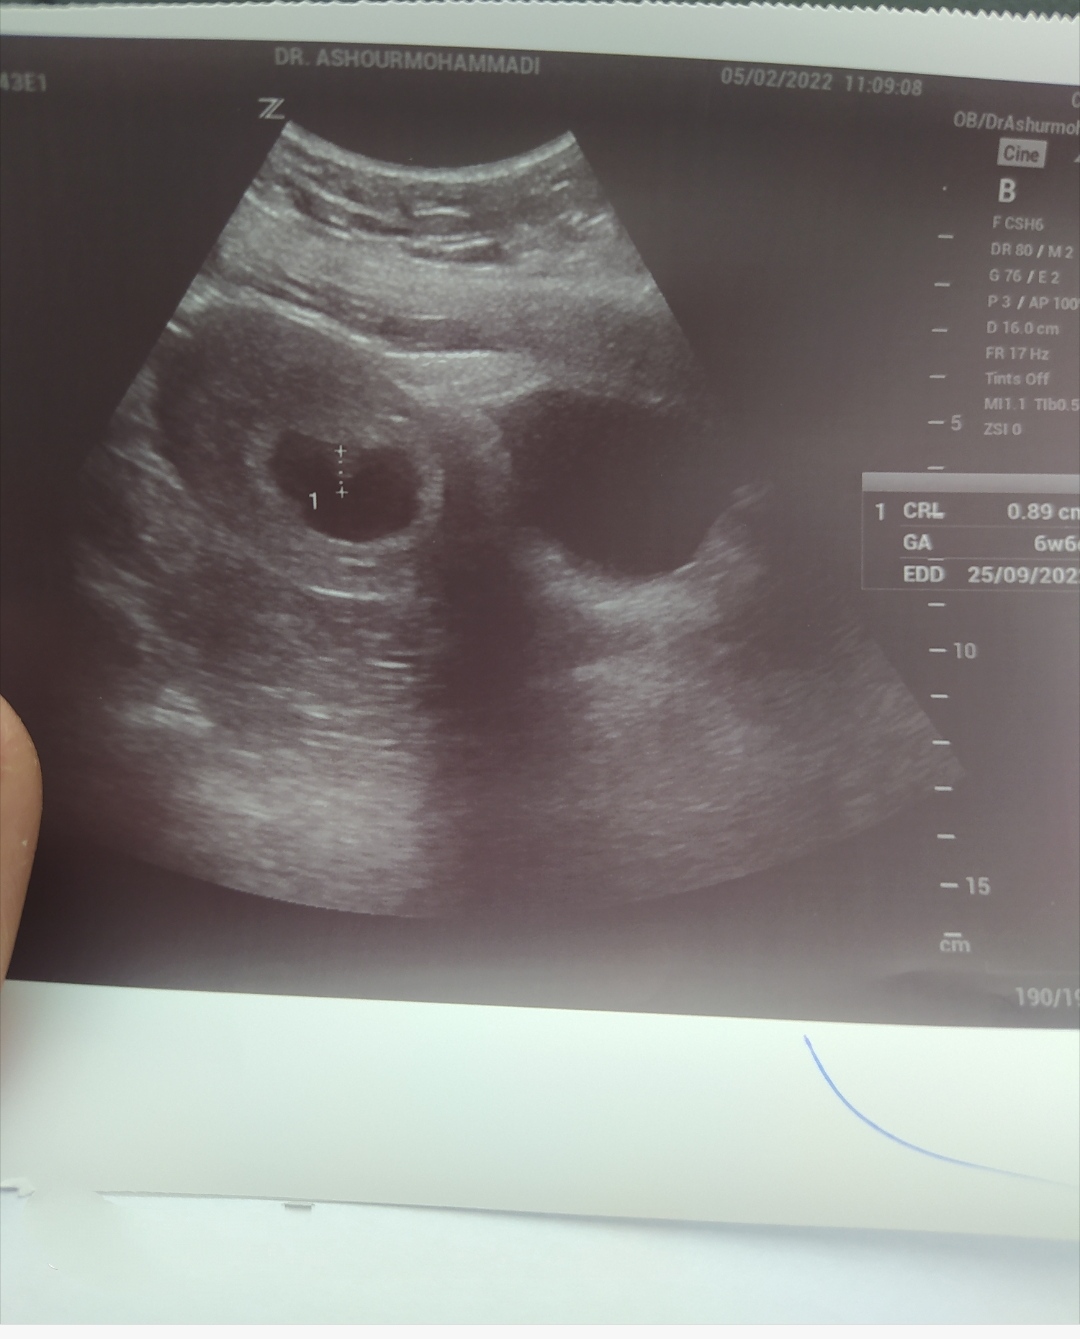

عکس سونو قلبی که رفتی را بزار تا بگم جنسیت را.البته اگه زیر۱۰هفته رفتی.

من میتونم بذارم عزیزم؟

سونو هشت هفتگیه

سونو واژینال یا شکمی؟

شکمی عزیزم

دختره عزیزم